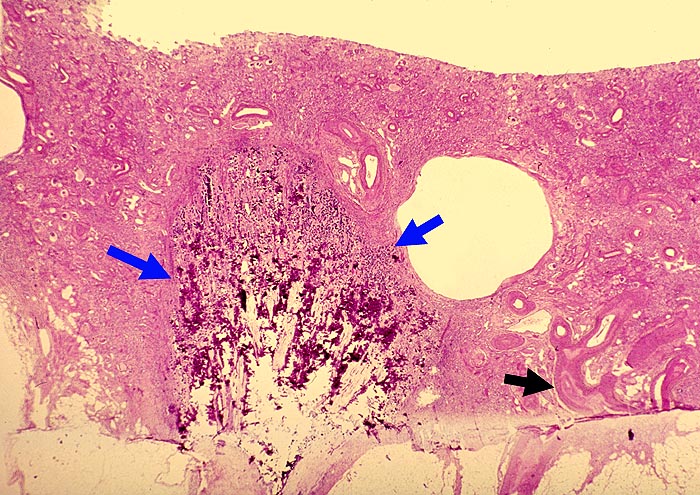

PathoPic – image database / PathoPic ID 1629 - Verknöcherte Papillennekrose bei Analgetikanephropathie

Verknöcherte Papillennekrose bei Analgetikanephropathie

Hochgradig geschrumpfte Nierenrinde. Die Tubuli sind vollständig atroph. Die gesamte nekrotische Papille ist in situ verblieben verkalkt und verknöchert. Die Gefässe zeigen eine ausgeprägte adaptative Intimafibrose.